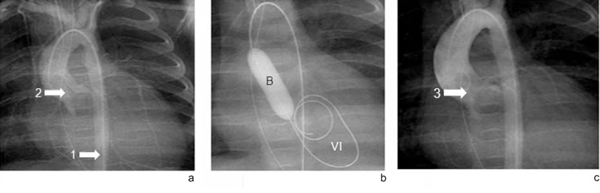

Caso 3: lactante de 4 meses, 5.600 g, procedente de Montevideo, producto de primera gestación sin antecedentes perinatales a destacar. PN 2.600 g, buen crecimiento y desarrollo, bien alimentada, portadora de estenosis aórtica diagnosticada desde el nacimiento catalogada de leve. Ingresa luego de paro cardiorrespiratorio en domicilio, reanimada por unidad de emergencia móvil que constata fibrilación ventricular. Se realizó ecocardiograma que mostró severa dilatación e hipocontractilidad del ventrículo izquierdo con válvula aórtica escasamente móvil y con escaso gradiente. Se interpreta como EVAo severa por lo que se efectúa valvuloplastia aórtica percutánea, con buena evolución (Figura 3).

Figura 3 a. Aortografía en proyección póstero-anterior. El catéter accede por vía arteria femoral-aorta descendente (flecha 1). Apertura en domo y mínima apertura sistólica de la válvula aórtica (flecha 2). b. Guía posicionada en ventrículo izquierdo (VI). Balón (B) totalmente expandido a nivel del anillo aórtico. c. Aortografía posvalvuloplastia con mejor apertura sistólica de la válvula aórtica (flecha 3).